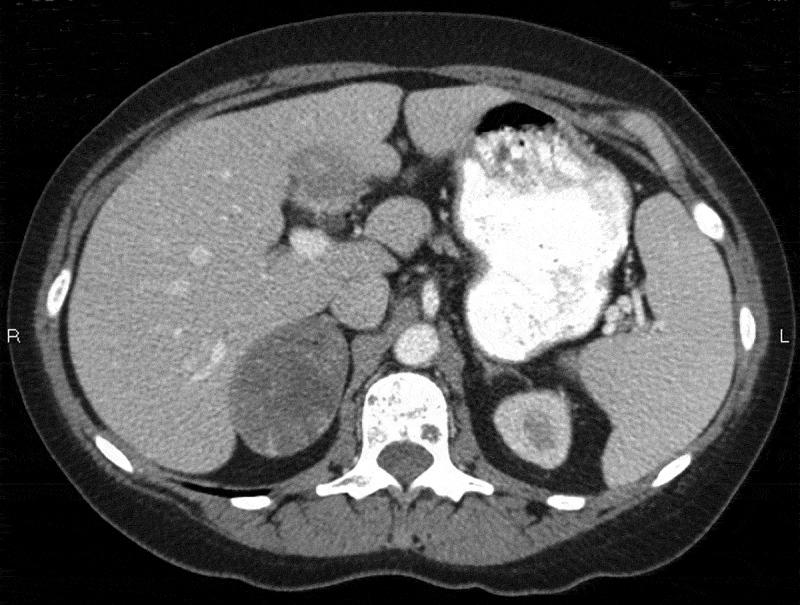

Adrenal collision tumors (ACTs), in which distinct tumors coexist without histological intermingling in the same adrenal gland, are rare and their actual prevalence is unknown. ACTs commonly consist of adrenal cortical adenoma, myelolipoma, or metastatic malignant tumor. We report a 58-year-old woman with a past history of breast cancer, who presented with a 1 month history of fevers, chills, and abdominal fullness. The physical examination and the laboratory data including endocrine studies were unremarkable. Computed tomography of the abdomen showed a right adrenal gland mass, and a laparoscopic right adrenalectomy was performed. Histological and immunohistochemical examinations revealed three distinct tumors: an adrenal cortical adenoma, a myelolipoma, and metastatic breast tumors. Breast cancer metastases are rare in the adrenal gland and exist as ACTs only in exceptionally rare cases. To our knowledge, this is the first reported case of coexisting metastatic breast tumors, adrenal adenoma, and myelolipoma in the same adrenal gland.

肾上腺碰撞瘤(ACTs)是指在同一肾上腺内不同肿瘤共存且无组织学混合,这种情况较为罕见,其实际患病率尚不清楚。ACTs通常由肾上腺皮质腺瘤、髓样脂肪瘤或转移性恶性肿瘤组成。我们报告一例58岁有乳腺癌病史的女性,她出现发热、寒战和腹部胀满1个月。体格检查及包括内分泌检查在内的实验室检查均无异常。腹部计算机断层扫描显示右肾上腺肿块,遂行腹腔镜右肾上腺切除术。组织学和免疫组化检查发现三种不同肿瘤:肾上腺皮质腺瘤、髓样脂肪瘤和转移性乳腺肿瘤。乳腺癌转移至肾上腺罕见,仅在极少数情况下以ACTs形式存在。据我们所知,这是首例报道的同一肾上腺内并存转移性乳腺肿瘤、肾上腺腺瘤和髓样脂肪瘤的病例。